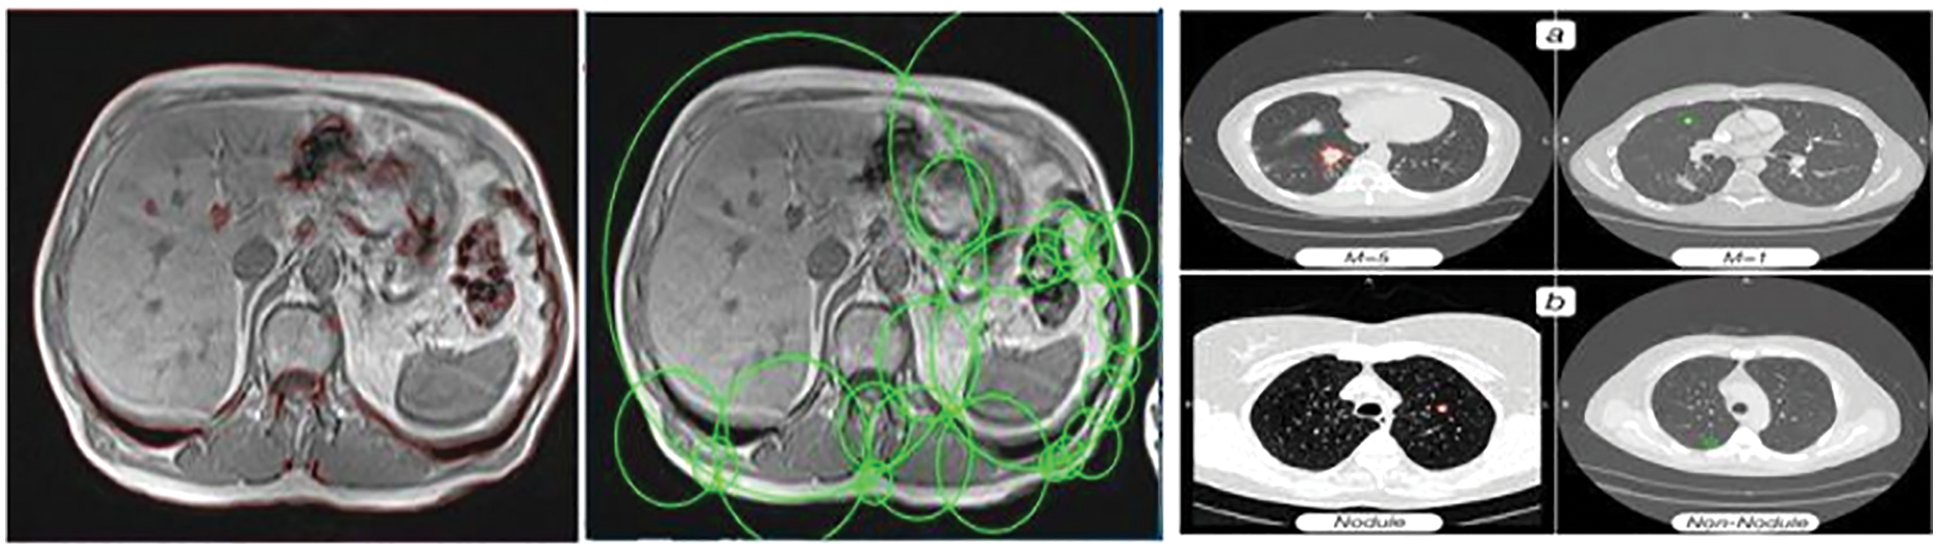

Cancer disease is a deadliest disease cause more dangerous one. By identifying the disease through Artificial intelligence to getting the mage features directly from patients. This paper presents the lung knob division and disease characterization by proposing an enhancement calculation. Most of the machine learning techniques failed to observe the feature dimensions leads inaccuracy in feature selection and classification. This cause inaccuracy in sensitivity and specificity rate to reduce the identification accuracy. To resolve this problem, to propose a Chicken Sine Cosine Algorithm based Deep Belief Network to identify the disease factor. The general technique of the created approach includes four stages, such as pre-processing, segmentation, highlight extraction, and the order. From the outset, the Computerized Tomography (CT) image of the lung is taken care of to the division. When the division is done, the highlights are extricated through morphological factors for feature observation. By getting the features are analysed and the characterization is done dependent on the Deep Belief Network (DBN) which is prepared by utilizing the proposed Chicken-Sine Cosine Algorithm (CSCA) which distinguish the lung tumour, giving two classes in particular, knob or non-knob. The proposed system produce high performance as well compared to the other system. The presentation assessment of lung knob division and malignant growth grouping dependent on CSCA is figured utilizing three measurements to be specificity, precision, affectability, and the explicitness.Keywords